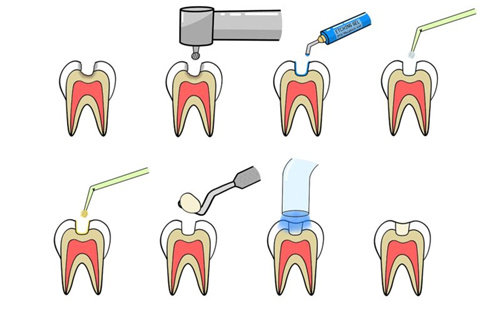

擅长领域:牙体牙髓病治疗、牙齿修复、牙列缺损修复等。